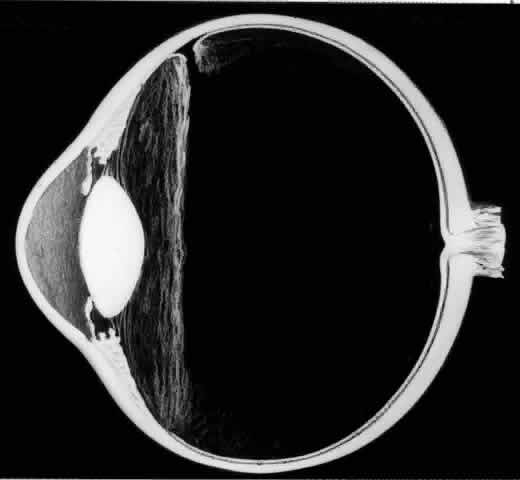

The earliest biomicroscopic changes preceding the development of a giant retinal tear were syneresis and liquefaction of the vitreous gel, converting the posterior and central portions of the vitreous body into a large lacuna (Fig. 14). Later, the anterior gel became condensed, and its posterior aspect formed an equatorially oriented membrane extending across the vitreous cavity (Fig. 15). This membrane did not oscillate with ocular movements, suggesting that it was under tension. Marked contraction of this membrane seems responsible for tearing the retina along the posterior border of the vitreous base (Fig. 16). Liquefied vitreous gel facilitated inversion of the posterior retinal flap (Fig. 17).

Fig. 15. In later biomicroscopic changes preceding a nontraumatic giant retinal break, the anterior vitreous gel becomes condensed and a membrane forms its posterior aspect.

Fig. 16. Contraction of this equatorially oriented membrane extending across the vitreous cavity produces a giant tear along the posterior border of the vitreous base.